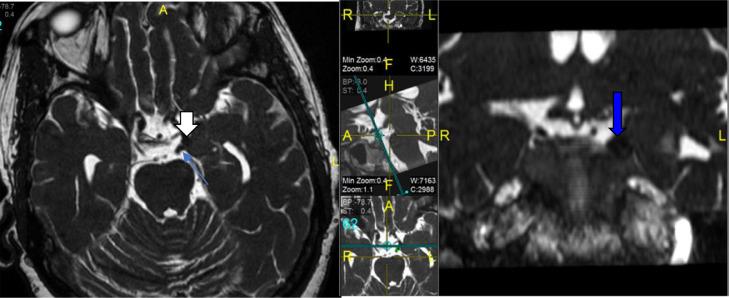

Posterior Communicating Artery Aneurysm in 20-year-old Female with Noonan's Syndrome.

West J Emerg Med. 2013 Mar;14(2):175-6. doi: 10.5811/westjem.2012.11.14368.

Oculomotor nerve palsy by posterior communicating artery aneurysms: influence of surgical strategy on recovery.

J Neurosurg. 2012 Nov;117(5):904-10. doi: 10.3171/2012.8.JNS111239. Epub 2012 Aug 31.